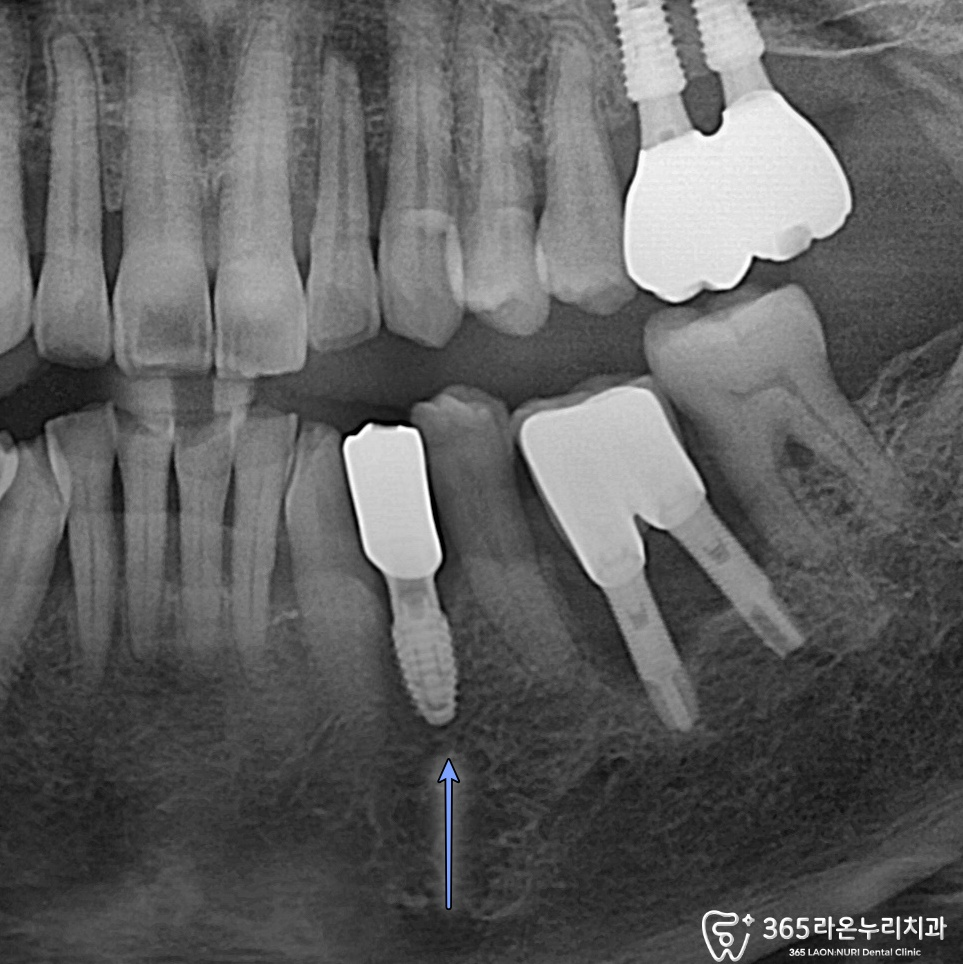

파노라마 엑스레이를

보았습니다.

치주염으로 치근단 염증 즉, 뿌리 주변으로

염증이 크게 번져가고 있었는데요.

표시해 드린 것처럼 염증이 크게 번지면서

치조골 및 치은이 크게 내려간 것을 알 수 있었죠.

(치조골/치은 퇴행)

식립된 모습을 보면

넓지 않은 공간에

잘 심겨져 있는 모습을 볼 수 있는데요.